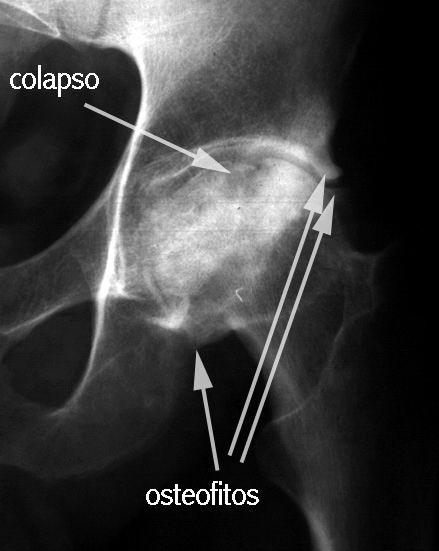

COLAPSO AFECTA LA SUPF SUBCONDRAL PERDIENDO SU MORFOLOGIA NORMAL

LA INCONGRUENCIA ARTICULAR PRODUCE PERDIDA DEL GROSOR DEL CARTILAGO Y CAMBIOS EN EL ACETABULO

EL

RADIOLOGIA